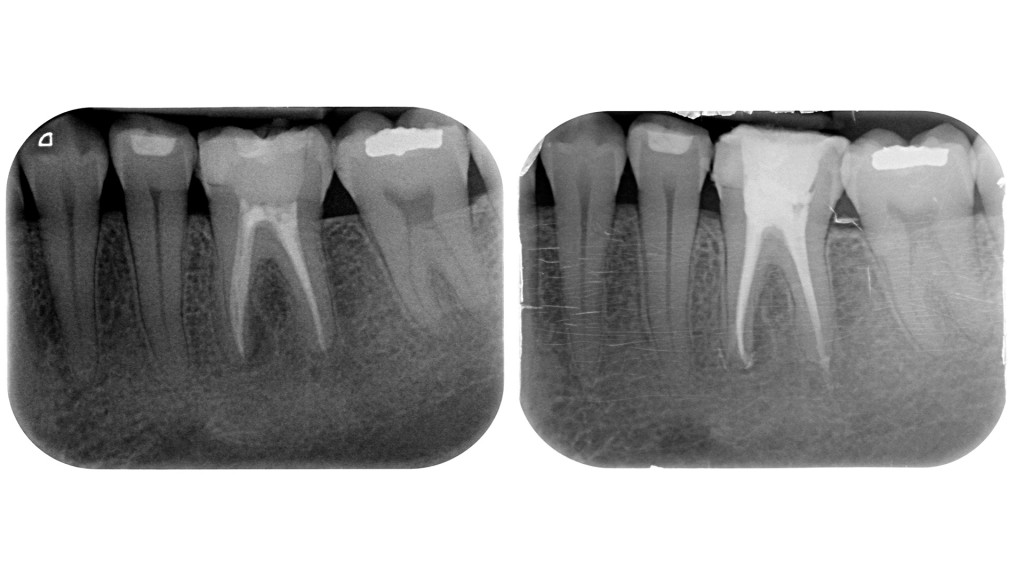

Azim & Co. Su 91 molari hanno trovato il canale MM in 42 casi! E 21 erano secondi molari!

Da allora su 48 primi molari ho trovato il canale mesiale-mediano 24 volte in 17 mesi! Percentuale di 50%!!!

E sto tenendo il conto solamente dei primi molari, ma come vedrai qui sotto, li trovo anche sui secondi molari inferiori.

Ho sempre cercato il canale mediano nella linea che congiunge il MV e il ML, l’ho trattato occasionalmente in pazienti giovani in cui lo vedevo già all’apertura della camera pulpare, ma non mi ero mai approfondita a cercarlo se non ne vedevo almeno un accenno, non avendo letto quell’articolo credevo che le percentuali fossero molto più basse.

Ora lo sto cercando con più convinzione approfondendomi come suggerito anche in casi in cui mi sembra in prima battuta che non sia presente e confermo che le percentuali di casi in cui lo reperisco sono leggermente aumentate!